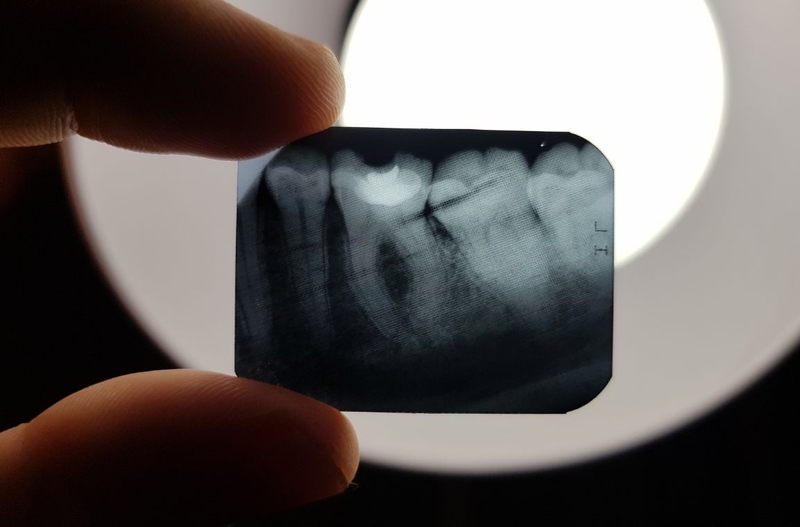

Chụp X quang răng là kỹ thuật chẩn đoán hình ảnh dùng máy chụp X quang phát ra tia X đi xuyên qua vùng răng cần chụp đến một tấm nhận. Tấm nhận này có thể là tấm phim hoặc tấm cảm biến kỹ thuật số, thường được đặt trong miệng người bệnh. Sau khi chụp, các kỹ thuật viên sẽ xử lý để thu được hình ảnh hoàn chỉnh.

Chụp X quang răng hiện có nhiều phương pháp hiện đại. Mỗi phương pháp sẽ có ưu điểm, tác dụng và mục đích khác nhau. Tùy vào mức độ tổn thương, vị trí răng cần chụp, mục đích của việc đánh giá tình trạng răng, các bác sĩ nha khoa sẽ chỉ định phương pháp chụp X quang răng khác nhau. Và một trong những kỹ thuật được áp dụng phổ biến nhất là chụp X quang răng cận chóp (kỹ thuật chụp X quang Periapical).